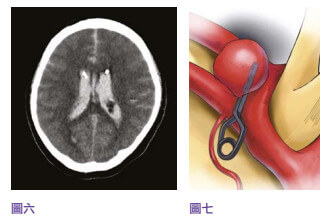

中风当时39岁的李先生三年前,39岁的李先生是位地盘工人,已婚育有一名幼子,为家庭经济支柱。 他身体一向健康,经常运动而且不烟不酒。 某日在工地里突然急剧头痛,继而晕倒在地。 工友立即召唤救护车将他送往附近的公立医院,送院时李先生还是半清醒。 电脑扫描显示他脑部有蜘蛛网膜下腔出血性中风(见图四),从造影可以看到一个约一至二毫米的动脉瘤在李先生大脑的前交通动脉血管之上(见图五)。 不幸的是,在医院观察的第二天早上,李先生突然深度昏迷,紧急电脑扫描显示动脉瘤第二次爆破,而且造成脑部严重积血、颅内压飙升,专科医生需要做紧急开颅手术去清除脑内血块,并将脑室引流以减低脑积水和颅内压(见图六),同时用钛金属夹将爆破的动脉瘤夹闭(见图七),防止它再次爆破。